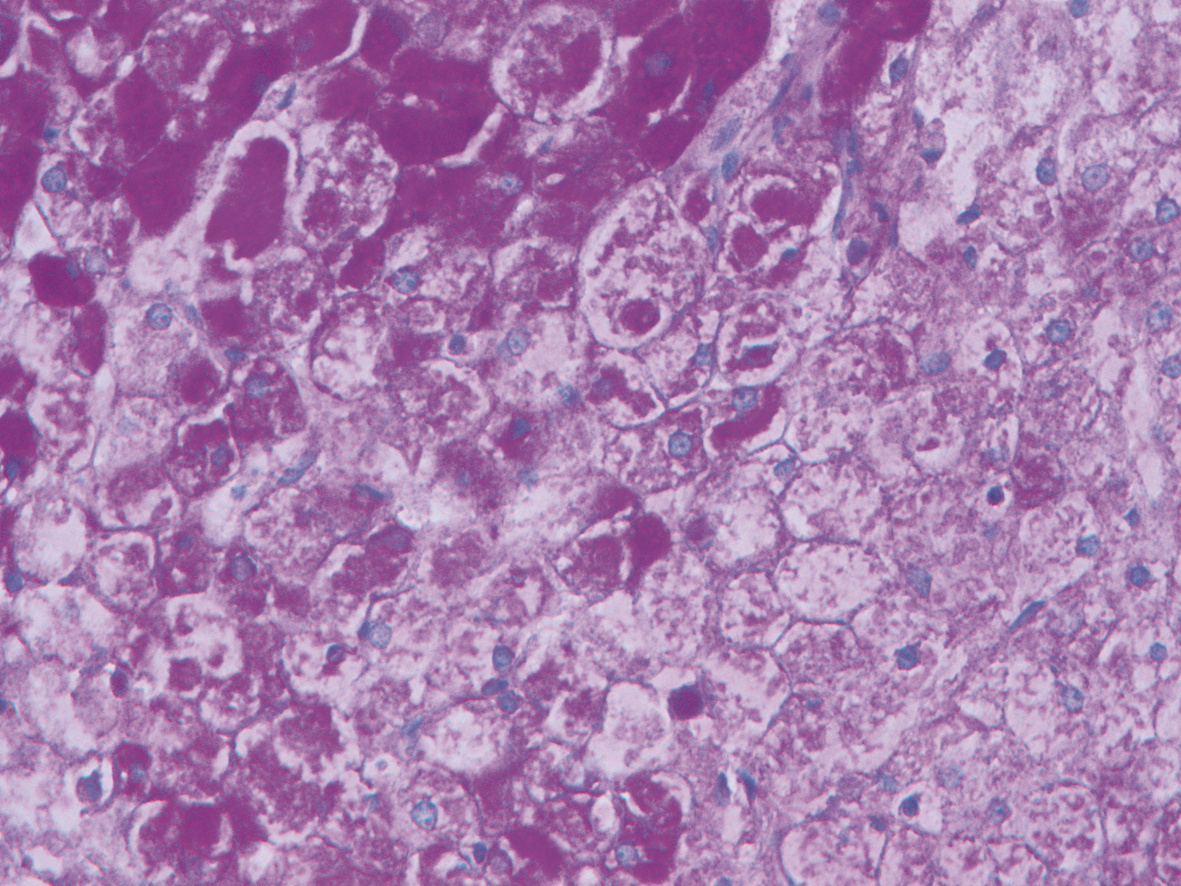

10例儿童肝糖原累积病临床及病理学分析

赵素贤, 刘世恒, 李文聪, 韩芳, 刘树红, 张庆山, 任伟光, 孔令波, 付娜, 王荣琦, 孔丽, 南月敏, 赵景民

2022, 38(8): 1839-1842. DOI: 10.3969/j.issn.1001-5256.2022.08.022

摘要(1409) HTML (513) PDF (2394KB)(109)

摘要:

目的  探讨儿童糖原累积病(GSD)的临床及病理学特点。  方法  选择2002年1月—2022年1月河北医科大学第三医院及解放军第五医学中心经病史、肝脏生化及肝活组织检查确诊的GSD 10例,对比分析人群特征、临床表现、生化指标、肝组织病理学特点。  结果  10例患儿发育迟缓,矮小,均表现为肝功能异常,轻度乏力、纳差、尿黄、眼黄,4例患者肝脾肿大。6例患者有低血糖的临床表现;1例患儿双侧腓肠肌肥大,Gower征阳性。2例患儿巨细胞病毒IgG阳性。肝组织病理学表现肝细胞弥漫性肿大,胞浆空淡,核小居中似植物细胞状,伴或不伴纤维组织增生。  结论  GSD患者多数有发育迟缓、转氨酶异常,肝组织病理检查有其特异性病理特征。